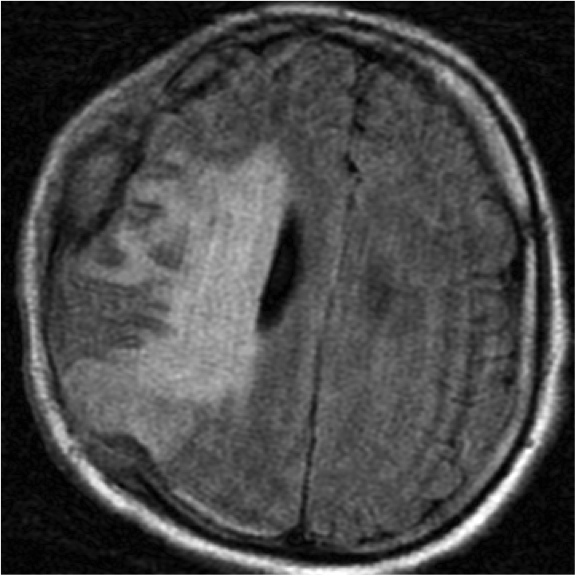

Subfalcina:

- Se produce la herniación de la circunvolución del cíngulo a través de la hoz.

- Puede producir compresión del asta y atrio del ventrículo ipsilateral.

- El VL contralateral puede dilatarse por obstrucción del agujero de Monro.

- Infartos del territorio anterior por compresión de la ACA y venas profundas.